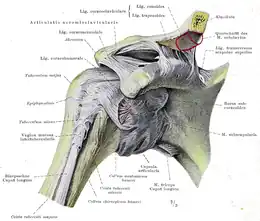

A : ligament acromio-claviculaire. B : acromion. C : ligament coraco-acromial. D : ligament coraco-huméral. E : tendon du long chef du biceps. F : tubercule mineur de l'humérus, ou trochin. G : capsule ligamentaire. H : processus coracoïde. I : ligament coraco-claviculaire (comportant le trapézoïde et conoïde). J : clavicule. K : tubercule majeur, ou trochiter

Le complexe articulaire de l'épaule met en relation quatre os :

- le manubrium sternal (ainsi que le premier cartilage costal) ;

- la clavicule ;

- l'omoplate (scapula) ;

- la tête humérale.

Articulation acromio-claviculaire

Également appelée « articulation cléido-scapulaire », l'acromio-claviculaire est une arthrodie. Elle ne possède donc aucun axe de rotation bien qu'un faible degré de mouvement existe. C'est une vraie articulation puisqu'elle possède une capsule articulaire, une synoviale et deux surfaces articulaires : celle de l'acromion et celle de l'extrémité latérale de la clavicule. Entre les deux surfaces articulaires, on retrouve un fibro-cartilage de type méniscal.

Cette articulation est stabilisée par quatre ligaments, de dehors vers dedans :

- Le ligament acromio-claviculaire qui relie les faces supérieures de l'acromion et de la clavicule ;

- Le ligament conoïde, tendu du processus coracoïde au tubercule conoïde de la clavicule ;

- Le ligament trapézoïde, tendu du processus coracoïde à la ligne trapézoïde de la clavicule ;

- Le ligament coraco-claviculaire médial, de moindre importance.